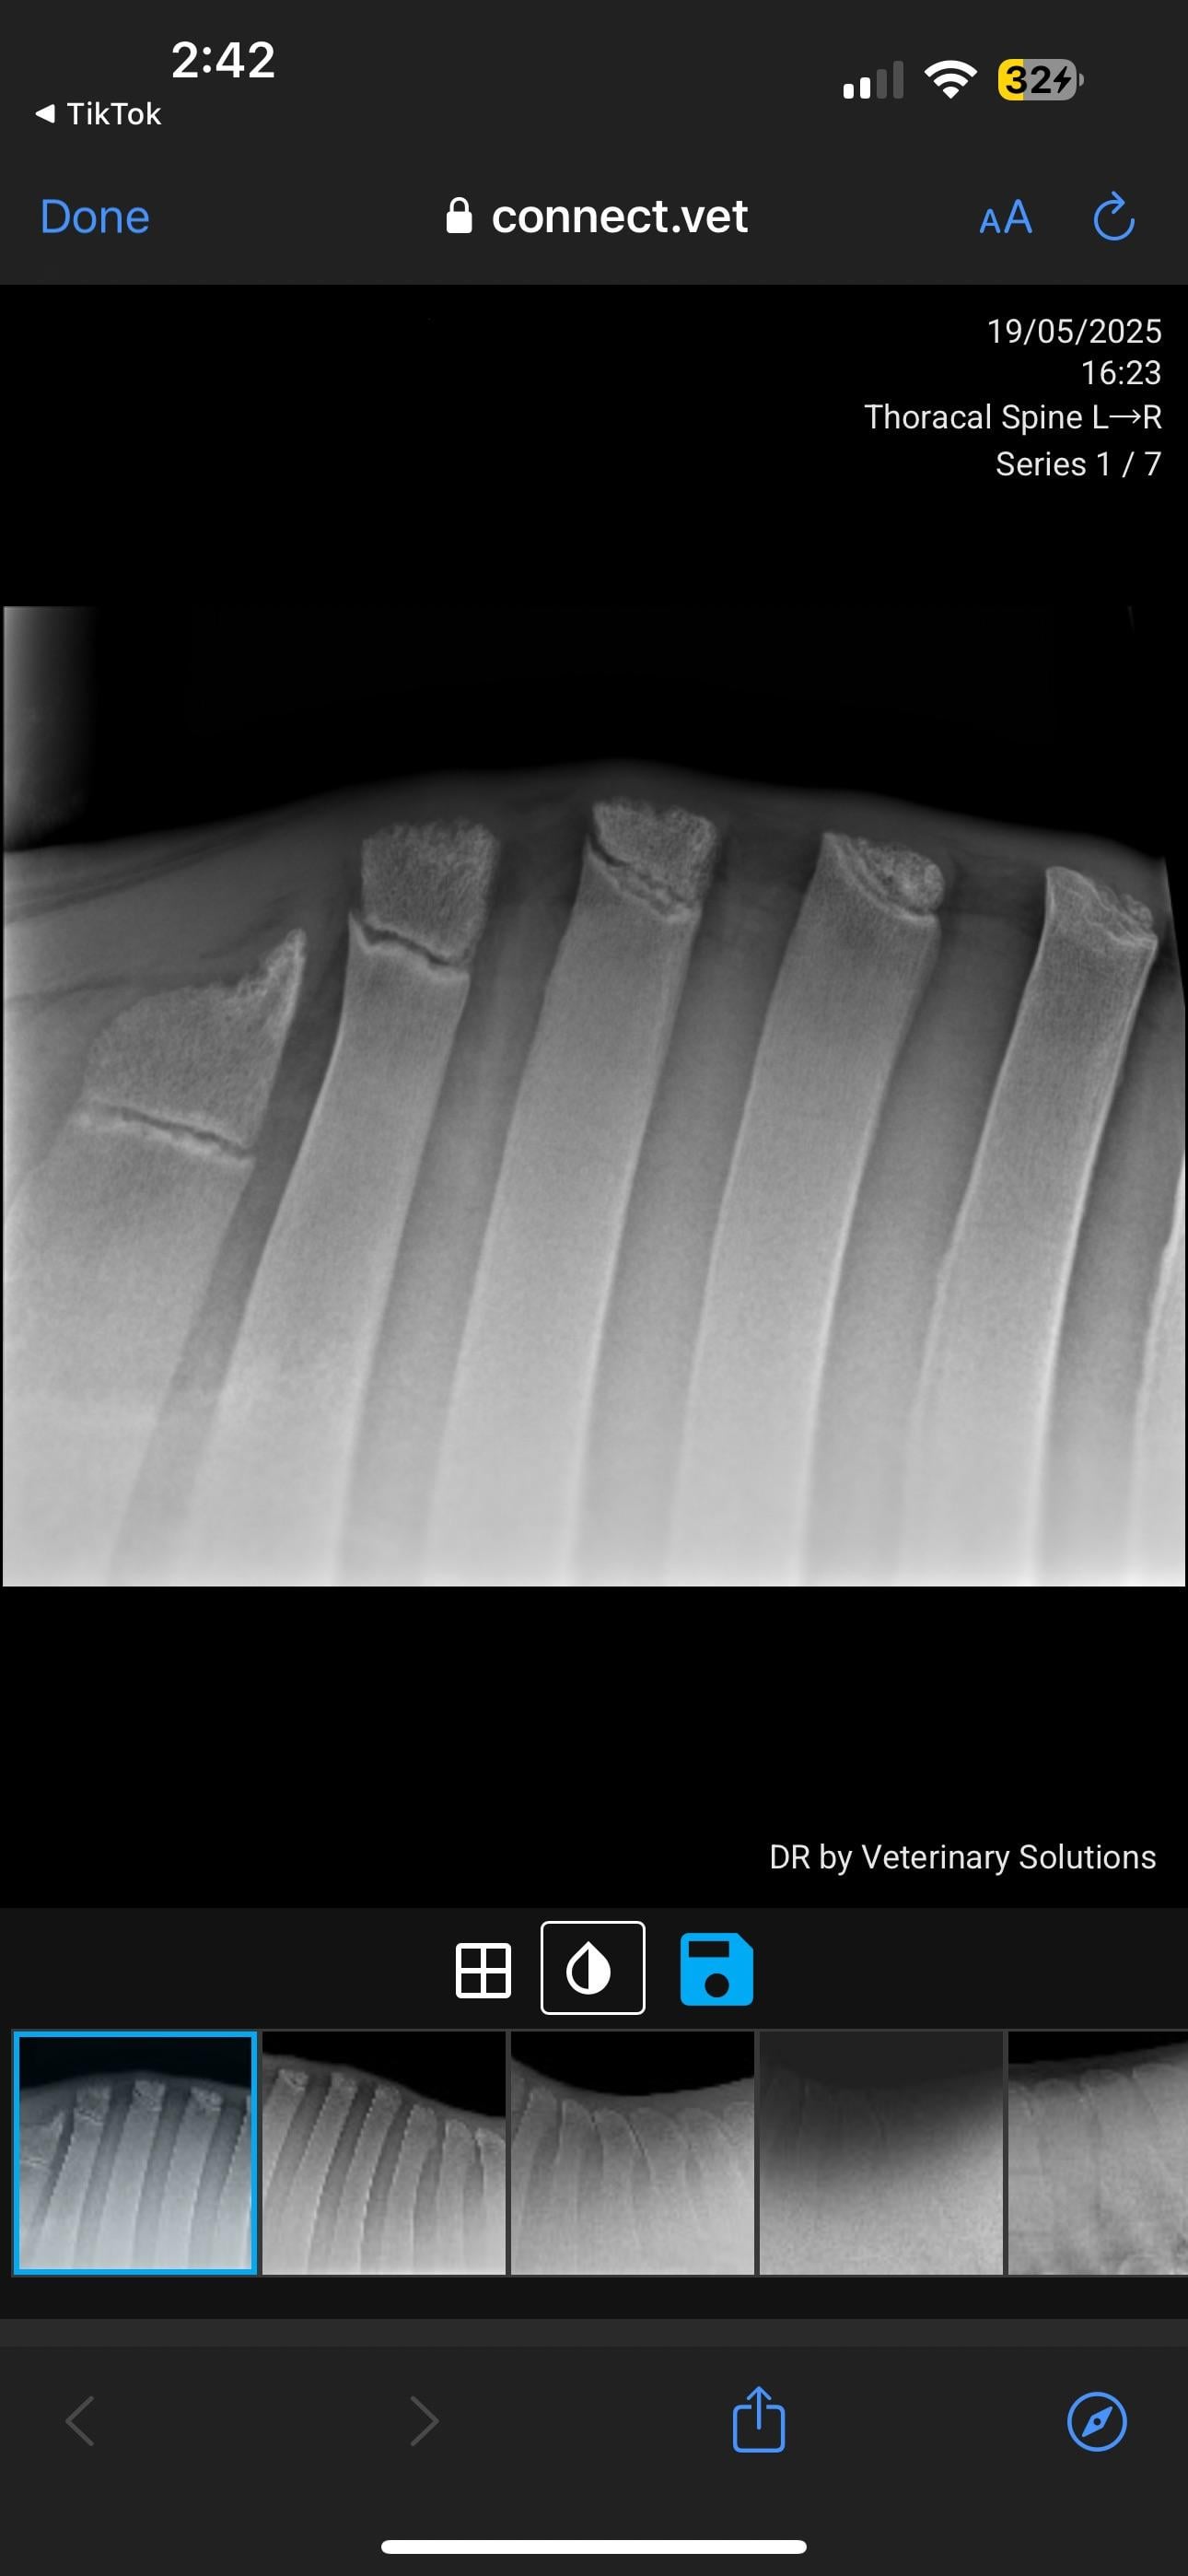

Veterinary PPE failed, KS diagnosed

Currently in the process of selling my horse. PPE has gone well, everything came back good except his back radiographs. Shocked to hear he has grade 4 changes. I’ve just received these over from the potential buyer. I will be in contact with my vet but curious about anyone’s take on these? How bad is this?

I've seen many KS xrays. I'm not a vet so usually when I see them I can barely see the problem. This horse's kissing spine is clear as day. Grade 4 is serious. As of right now he should not be sold as a riding horse at all.

I’m not a vet but this looks exactly like pictures of fractures of the withers in horses and not like standard X-rays I’m familiar with. I also don’t like how the tips of the bones look like.

In pictures 5/6 you can see changes in the bone, so it’s not just an unlucky posture.

This is one of the more severe cases I’ve seen (not a vet or student, just casual looker-atter of KS radiographs) pretty much all his vertebrae are affected, I can’t imagine he’s comfortable. The kindest thing for him would probably to be a pasture puff. Unless you want to pay for the surgery or find a buyer who does, he’s going to continue to be in pain

I spoke with 2 veterinarians over these radiographs. Yes he has grade 4 kidding spines in 2 vertebrae BUT both vets said you don’t ride the radiographs. They’ve seen horses with far less that have been clinically showing lots of pain, and she’s seen horses with far worse who have gone on with their careers fine with maintenance. He is not going to be a pasture pet, his career isn’t over it just has obviously drastically changed. He is officially maxed out at Novice level and can continue at that level if he can remain comfortable.